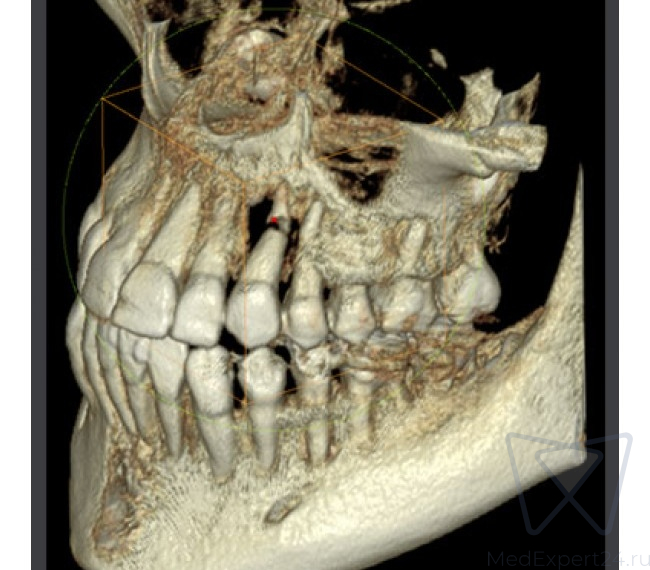

Возможности компьютерного томографа:

- Отдельный сенсор для 3D исследований

- Стандартный режим работы

- Изображения высокой четкости для эндодонтического лечения

- Хирургический режим работы

- Имплантационный режим работы

- Высококачественная панорамная томограмма

- Регулировка толщины среза

- Регулировка плотности тканей

- Денсинометрия

- Кубическое ограничение зоны визуализации

Оптимальный размер области исследования (9x9 см) и разрешение 143 μm